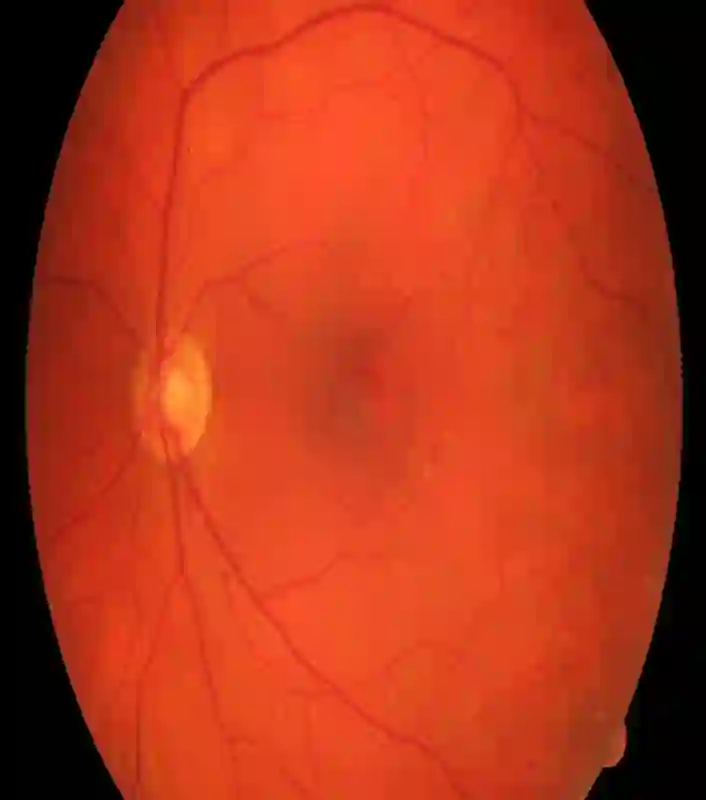

Retinal artery/vein (A/V) classification is a critical technique for diagnosing diabetes and cardiovascular diseases. Although deep learning based methods achieve impressive results in A/V classification, their performances usually degrade severely when being directly applied to another database, due to the domain shift, e.g., caused by the variations in imaging protocols. In this paper, we propose a novel vessel-mixing based consistency regularization framework, for cross-domain learning in retinal A/V classification. Specially, to alleviate the severe bias to source domain, based on the label smooth prior, the model is regularized to give consistent predictions for unlabeled target-domain inputs that are under perturbation. This consistency regularization implicitly introduces a mechanism where the model and the perturbation is opponent to each other, where the model is pushed to be robust enough to cope with the perturbation. Thus, we investigate a more difficult opponent to further inspire the robustness of model, in the scenario of retinal A/V, called vessel-mixing perturbation. Specially, it effectively disturbs the fundus images especially the vessel structures by mixing two images regionally. We conduct extensive experiments on cross-domain A/V classification using four public datasets, which are collected by diverse institutions and imaging devices. The results demonstrate that our method achieves the state-of-the-art cross-domain performance, which is also close to the upper bound obtained by fully supervised learning on target domain.